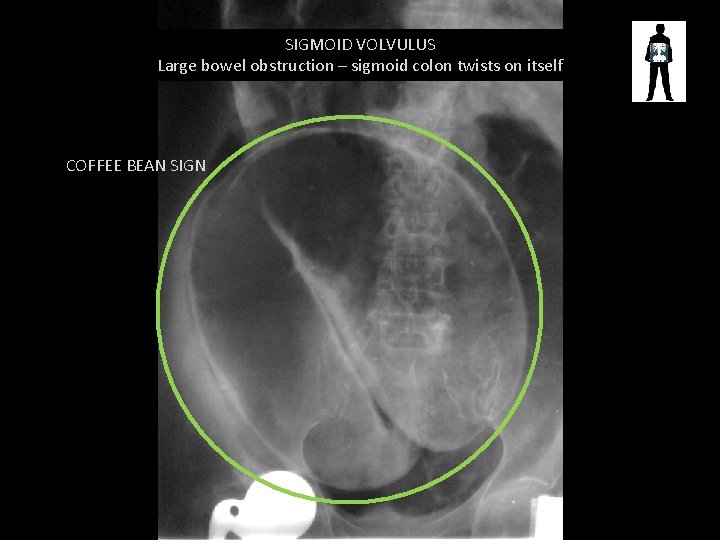

SIGMOID VOLVULUS Large bowel obstruction – sigmoid colon twists on itself COFFEE BEAN SIGN

Sigmoid Volvulus • Caused by long-term chronic constipation • More common in older patients and males • Can cause complete vascular disruption to bowel wall, obstruction and perforation • Perforation -> peritonitis ->danger